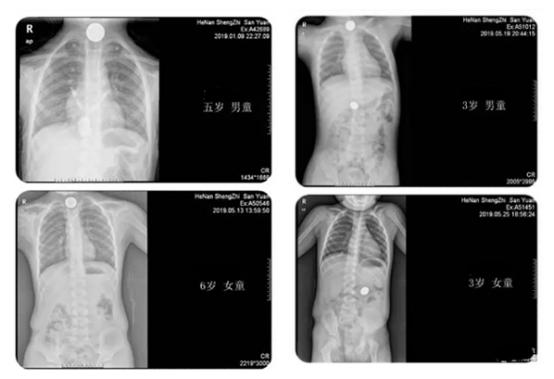

从图上可以看出,左面两个显示硬币在食管第一狭窄处,右上显示食管第一狭窄和胃腔均有,第四个显示在胃腔。因硬币较大,嵌顿食管第一狭窄处或滞留胃腔,患儿无法自行排出,根据患儿年龄、一般情况、硬币嵌顿时间及嵌顿部位,我科联合麻醉科制定缜密的治疗方案,行全麻下消化内镜异物取出术。